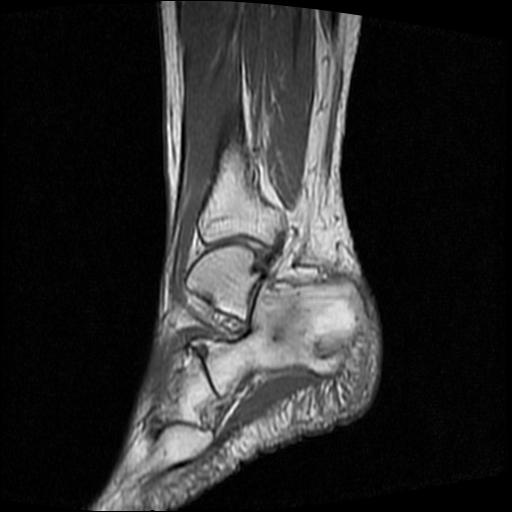

标题: MRI0968:女性,70岁,跟骨信号异常 [打印本页]

标题: MRI0968:女性,70岁,跟骨信号异常

女性,70岁,右侧跟骨疼痛2个月,负重时加剧,不负重时不疼。

胫骨下段,跟骨、距骨可见斑片状异常信号区;考虑:转移瘤

跟骨长t1长t2信号异常,边缘模糊(肿瘤一般边界清楚,故肿瘤不考虑),压脂像呈高信号--骨髓水肿(炎症?)。